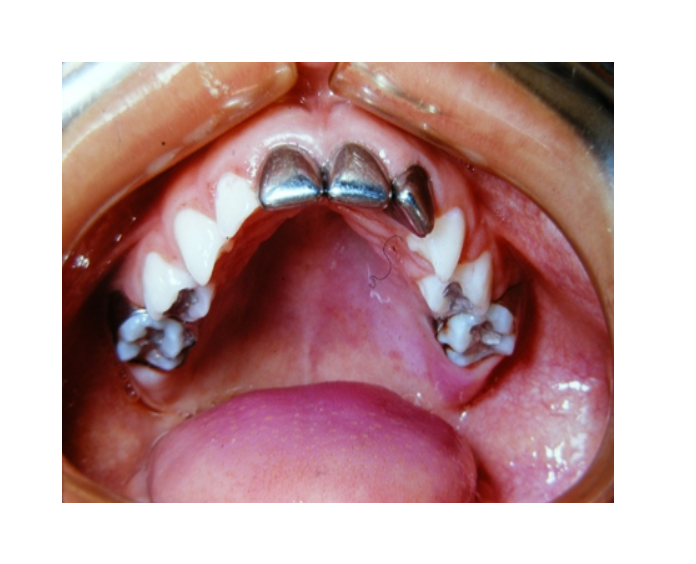

Mordida Cruzada posterior unilateral